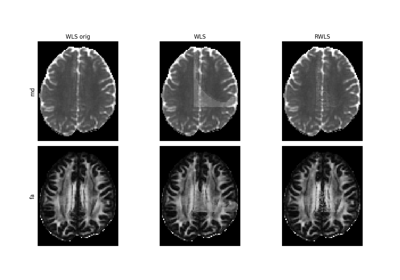

Using the RESTORE algorithm for robust tensor fitting